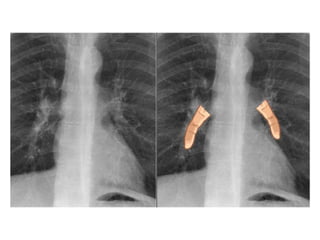

Transverse image of the normal

appendix without (left) and with

• LEFT: The normal appendix is small,

compressible, contains no Doppler signal, and

is not surrounded by inflamed fat .RIGHT: The

inflamed appendix is large, non-compressible

and hypervascular, and is surrounded by

hyperechoic, non-compressible tissue,

representing the fatty mesoappendix

Transverse image ofthe normal appendix without (left) and with compression (right)

• LEFT: Thenormal appendix is small, compressible, contains no Doppler signal, and is not surrounded by inflamed fat .RIGHT: The inflamed appendix is large, non-compressible and hypervascular, and is surrounded by hyperechoic, non-compressible tissue, representing the fatty mesoappendix